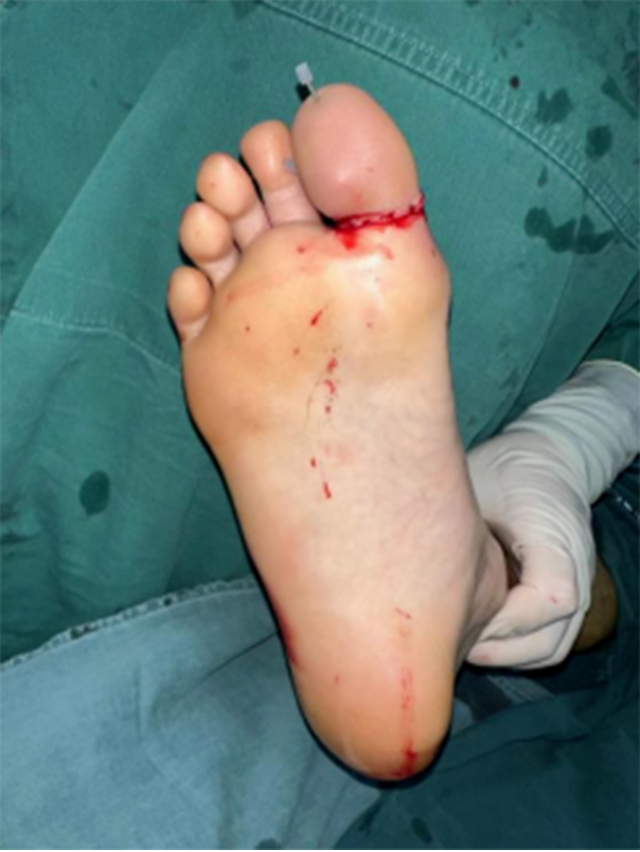

周末一大早,30岁的小李在家中用切割机锯木条。为了稳定木块,小李右脚用力踩着木块。突然,锯条断裂,锋利的锯条瞬间将小李右脚大拇趾切断,第二根脚趾被切了一半,剩下一半还悬在脚上,疼痛剧烈、出血不止,家人赶紧用毛巾止血,用口袋把断掉的大拇趾装好,将小李送到附近医院。

16:45,手术开始。麻醉、消毒、清创、止血……

相较于手指断裂,脚趾断裂的手术难度更大,因为手术时手指更容易摆成方便医生操作的体位,而脚趾没那么灵活。显微镜下,黄宇仔细缝合一根根断掉的神经和血管,每吻合一根,都要检查血供情况。

手术历时7个多小时,直到半夜12点才结束。术后予以抗感染、抗血管痉挛、补液扩容等治疗。最终保住了小李右足的两根脚趾。